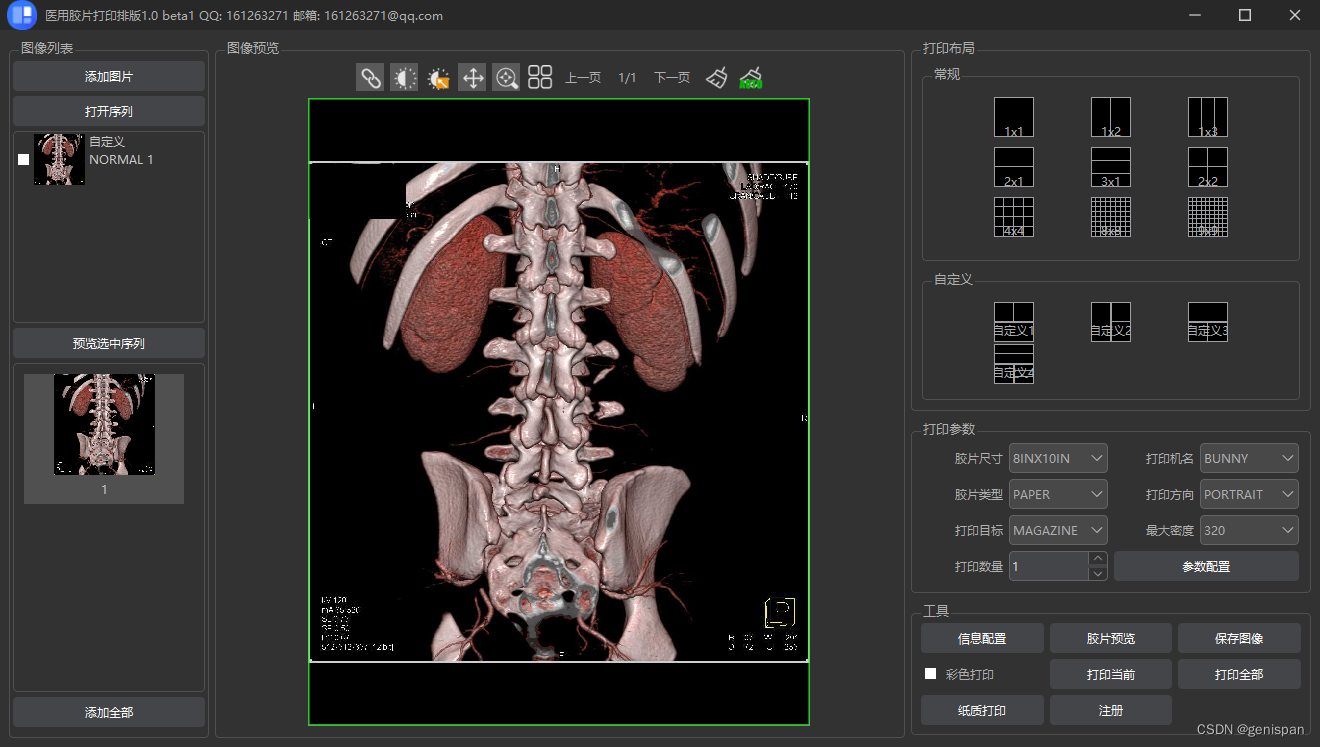

灰度图像打印:

彩色图像打印:

文章详细介绍了DICOM图像的两种打印类型——灰度图像和彩色图像,包括DICOM图像的关键元数据如像素信息、窗宽窗位等。在组建待打印的数据集时,涉及了如何设置各种参数。此外,还讨论了使用Qt库构建RGB图像数据的过程,以及图像对齐和分页打印的策略。最后展示了打印效果的预览。

文章详细介绍了DICOM图像的两种打印类型——灰度图像和彩色图像,包括DICOM图像的关键元数据如像素信息、窗宽窗位等。在组建待打印的数据集时,涉及了如何设置各种参数。此外,还讨论了使用Qt库构建RGB图像数据的过程,以及图像对齐和分页打印的策略。最后展示了打印效果的预览。